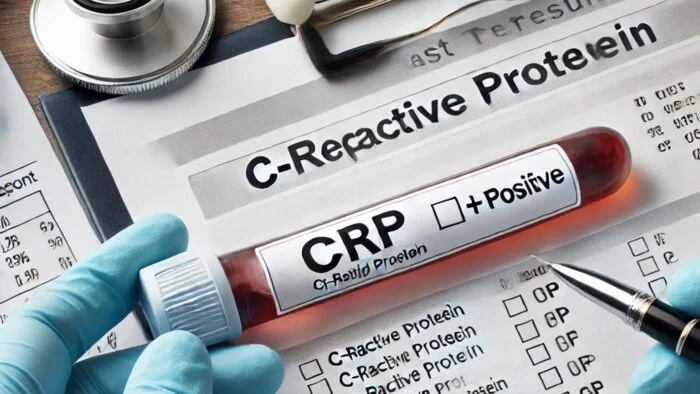

آیا CRP مثبت خطرناک است؟

آزمایش CRP یکی از آزمایشهای مهم برای بررسی سطح التهاب در بدن است. بسیاری از افراد هنگام دریافت نتیجه آزمایش خود با عبارت CRP مثبت مواجه میشوند و این سوال برایشان پیش…

آیا CRP مثبت خطرناک است؟

آزمایش CRP یکی از آزمایشهای مهم برای بررسی سطح التهاب در بدن است. بسیاری از افراد هنگام دریافت نتیجه آزمایش خود با عبارت CRP مثبت مواجه میشوند و این سوال برایشان پیش میآید که آیا CRP مثبت خطرناک است؟ سطح بالای CRP میتواند…